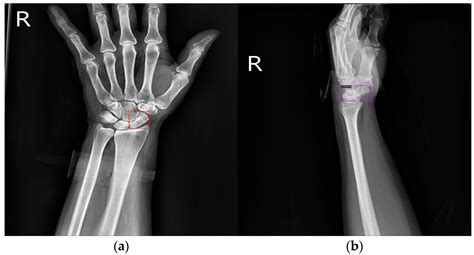

A scaphoid bone fracture is one of the most common carpal bone injuries in the wrist, often resulting from a fall onto an outstretched hand. Located on the thumb side of the wrist, the scaphoid is a small, boat-shaped bone that plays a crucial role in wrist stability and movement. Because of its unique blood supply, which can be easily disrupted by an injury, this specific fracture requires prompt medical attention to avoid long-term complications. Ignoring symptoms or dismissing the injury as a simple sprain can lead to chronic pain, loss of function, and the development of arthritis.

The scaphoid bone is situated at the base of the thumb and acts as a bridge between the two rows of wrist bones. When you fall forward, your instinctive reaction is to land on an outstretched hand. This sudden impact forces the wrist into hyperextension, putting immense pressure on the scaphoid bone. If the force is significant enough, the bone may crack or break completely.

Because a scaphoid bone fracture does not always appear on an initial X-ray, doctors often rely on clinical examination and follow-up imaging. If a doctor suspects a fracture despite clear X-rays, they may immobilize the wrist and order repeat imaging in one to two weeks. During this time, the fracture line often becomes more visible as the bone begins to resorb.

X-ray Imaging Primary scan to identify major breaks or displacement.

MRI or CT Scan Used for occult fractures that are hidden on standard X-rays.

Treatment for a scaphoid bone fracture depends heavily on the location of the break. The scaphoid has three parts: the proximal pole (closest to the forearm), the waist (the middle part), and the distal pole (closest to the thumb). Breaks in the middle or toward the thumb usually heal well with immobilization, while breaks near the proximal pole are more prone to complications because they have a poorer blood supply.